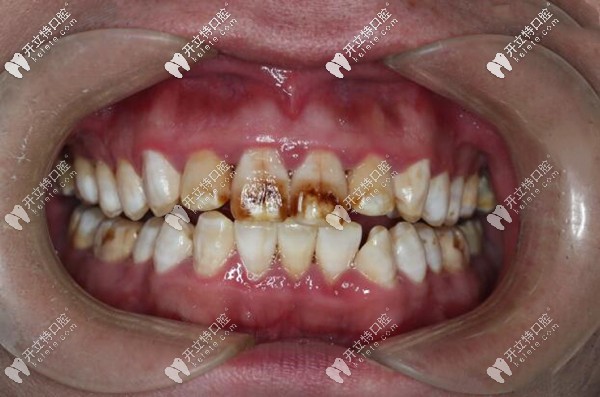

重度氟斑牙清晰圖片▼

我的重度氟斑牙清晰圖片